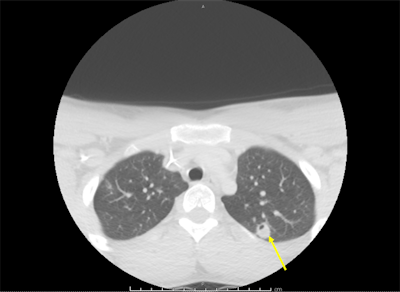

A neck ultrasound revealed a thrombosed superficial internal jugular vein consistent with thrombophlebitis, and a repeat chest x-ray showed right lung opacities indicating pneumonitis. A CT angiography (CTA) scan showed scattered nodular-appearing infiltrates throughout his lungs and moderate bilateral effusion. His blood tested positive for F. necrophorum.

Though the initial CTA failed to show pulmonary emboli, a subsequent CT scan showed evolving cavitation of the multiple nodular densities seen on the initial chest x-ray. The findings were consistent with septic pulmonary emboli. A vascular surgeon recommended that the teen's condition be managed without surgery.